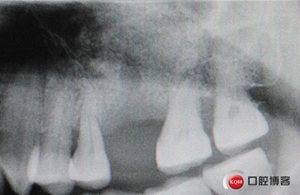

術(shù)后X光片,植骨量充足。

術(shù)后8個月,X光顯示骨量充足,密度明顯增加。

植入后X光片。